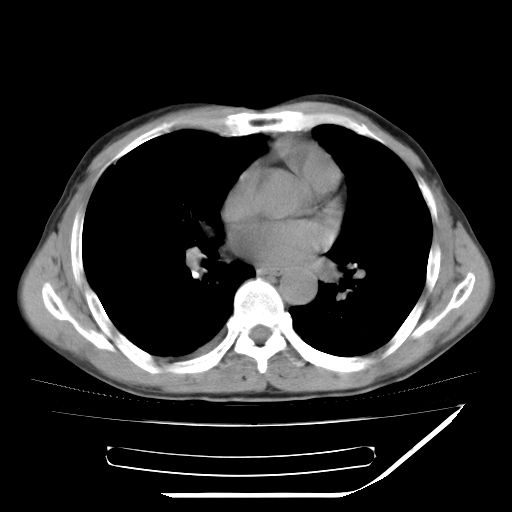

男,59岁,“结核性胸膜炎”30余年,胸部经常疼痛,多次x检查提示“肺部”炎症。腹部疼痛5日,b超提示:“肝内短管结石,余显示不清,建议进一步检查。”

两肺结核并右侧胸腔积液;脾脏、腹腔及腹膜后淋巴结结核[陈旧性];肝内胆管结石

胸部腹部都是结核(双肺。纵隔淋巴结,肝脏,脾脏,肠系膜)

两肺结核并右侧胸腔积液;脾脏、腹腔及腹膜后淋巴结结核[陈旧性];肝内胆管结石。直肠息肉?